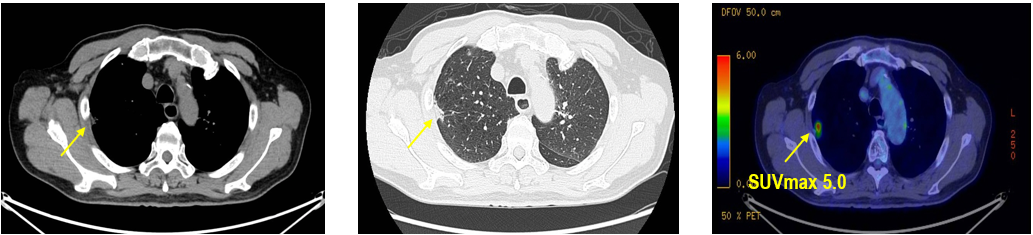

CT及PET-CT随访(2023年11月、2024年1月):评估新辅助治疗效果,右下肺叶肿块缩小,右肺门淋巴结代谢活性消失,右肺上叶结节稳定但代谢活性降低,左肺上叶及双侧磨玻璃样病变稳定。